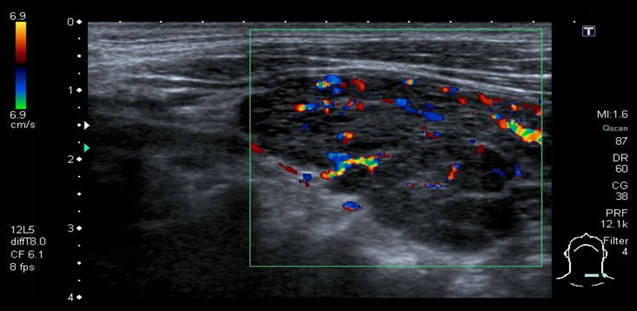

Color-coded duplex sonography of the thyroid

There are hypoechoic and heterogeneous thyroid parenchyma and an enlarged thyroid.

There is no increased vascularization or perfusion in the color-coded duplex ultrasound. - These findings are consistent with the

Acute stage of Hashimoto thyroiditis.